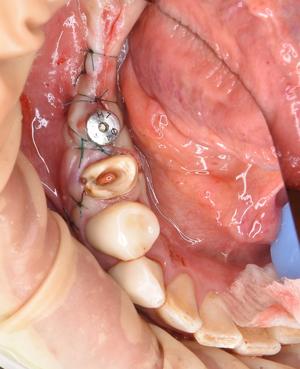

切開して開けてみると、2ヶ月前の抜歯跡が見受けられた。しかし

当院では骨の再生治療をインプラント移植時に同時進行で施しているので、全く問題はありません。

骨のない所に人工骨のβ–TCPを添加して、本物の骨に置換するのを待ちます。

左下の施術終了。